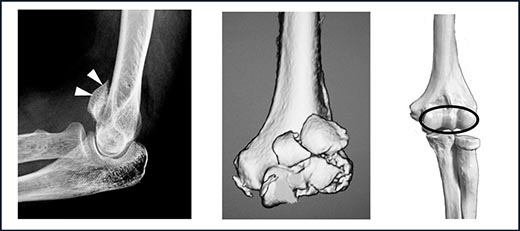

- 上腕骨小頭・滑車骨折(〜しょうとう・かっしゃこっせつ)

上腕骨小頭のみの骨折や上腕骨小頭と滑車の両方が骨折している場合があります(図4)。立った位置からの転倒など軽微な力で骨折することも多く、骨粗鬆症のある女性や高齢の方に多く発生します。上腕骨の関節面に、橈骨が突き上げるような外力が加わるため上方に転位(ズレ)していることが多く、ギプスで固定しても骨はつきません。

図4.上腕骨小頭・滑車骨折:レントゲン像で骨片(矢印)が上方に転位しています。